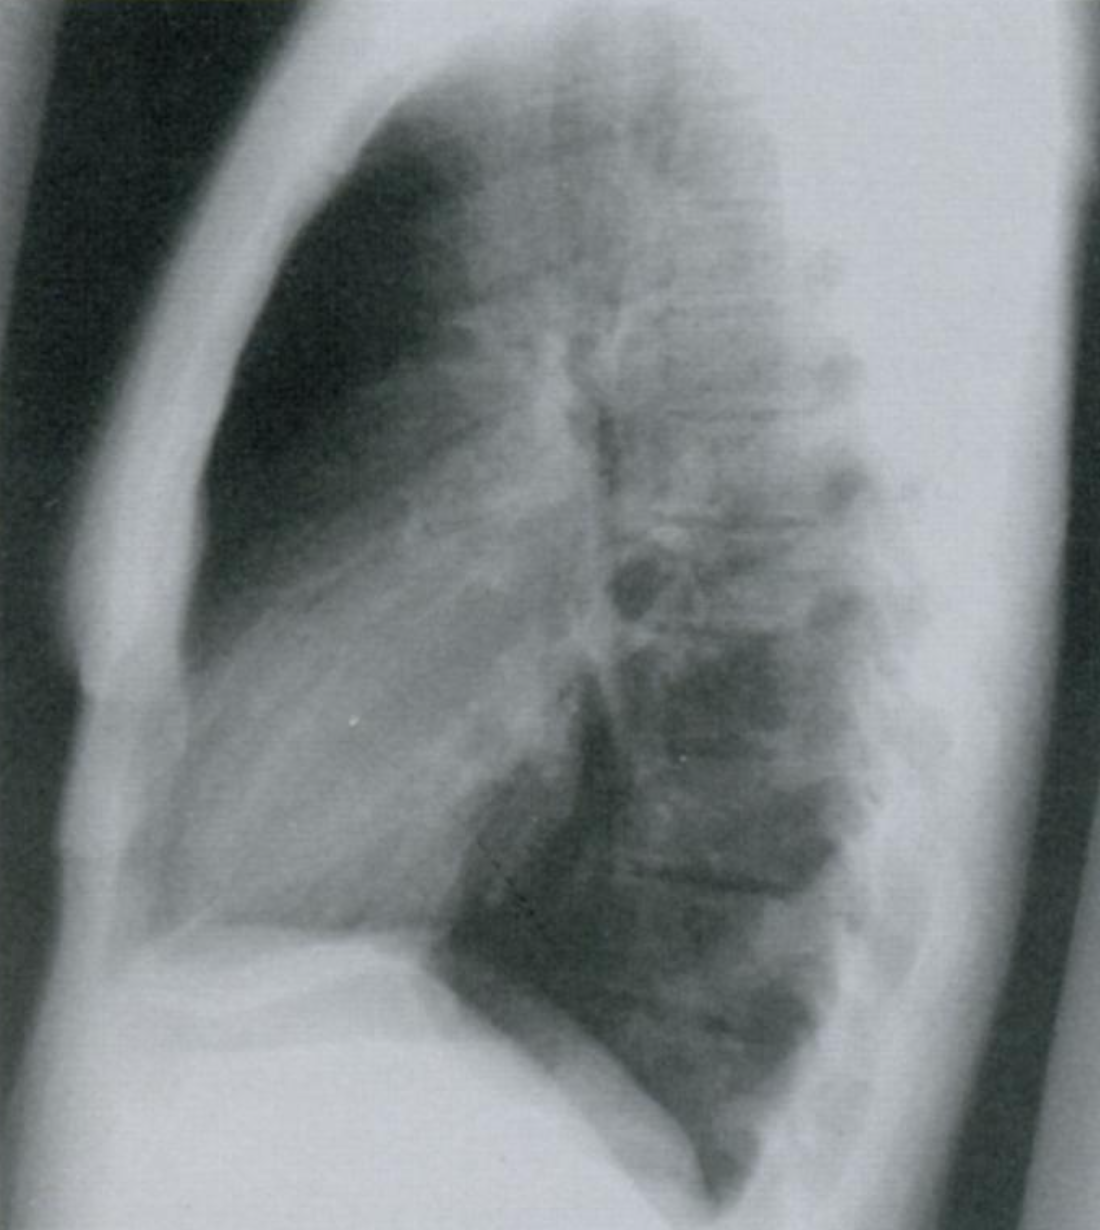

21

Q

Что отмечено стрелками на снимке?

Что такое линии Кёрли? Какие типы Вы знаете?

Интерстициальные заболевания легких характеризуются ретикулоузловой картиной паутиноподобных затенений из-за наложения отечных междольковых перегородок + мелкоочаговых затенений с четкими границами.

A

Поверхностные лимфатические протоки легких, в даном случае с признаками застоя походу междольковых перегородок.

На снимке становятся видны в виде линий, которые мы называем линиями Керли. В даном случае линии Керли типа В (короткие линейные затенения 1-2 см. в сублевральной области (на периферии полей легких) в нижнем или среднем отделе легких.

Линии Керли типа А более длинные (до 5 см.), идут от корней легких в верхней доле.

Есть карточка с делением легких на отделы (отделы - не доли, а как бы три этажа легочного поля, чтобы более понятно описывать локализацию структур именно на снимке).